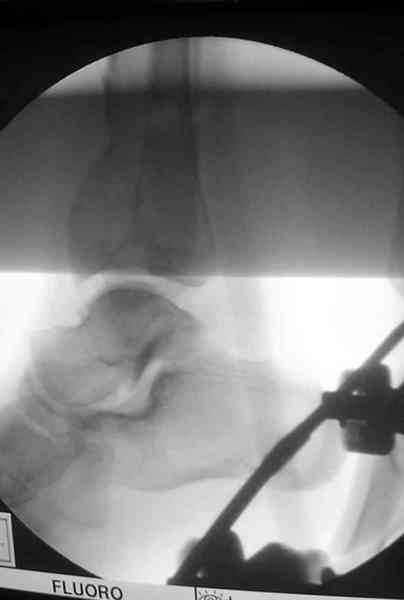

В первые часы после поступления больным экстренно накладывается простой фиксатор из двух поперечно проведенных стержней или сооружается "Delta

Frame" в зависимости от места локализации, и проводится дистракция.

Преимуществ у временного фиксатора много, во первых больной независим, если по другим показаниям нет необходимости находиться в стационаре, то больной может быть выписан домой с возможностью в амбулаторных условиях оценивать состояния мягких ткани на готовность к операции.

Наружным фиксатором обеспечивается длина конечности, предупреждается вторичное сокращение мягких ткани, что является немаловажным фактором для заживления послеоперационных ран. Без фиксатора сокращенные мягкие ткани легко травмируется во время манипуляций, трудно будет провести репозицию, ухудшается местное кровообращение и сохраняется посттравматический отек.

Дистрагированные лигаментотаксисом костные фрагменты иногда организуются в нужном направлении и во время операции облегчается репозиция отломков.

Здесь выставлена пара случаев перелома пилона, оба

случая леченные этапным наружным фиксатором.